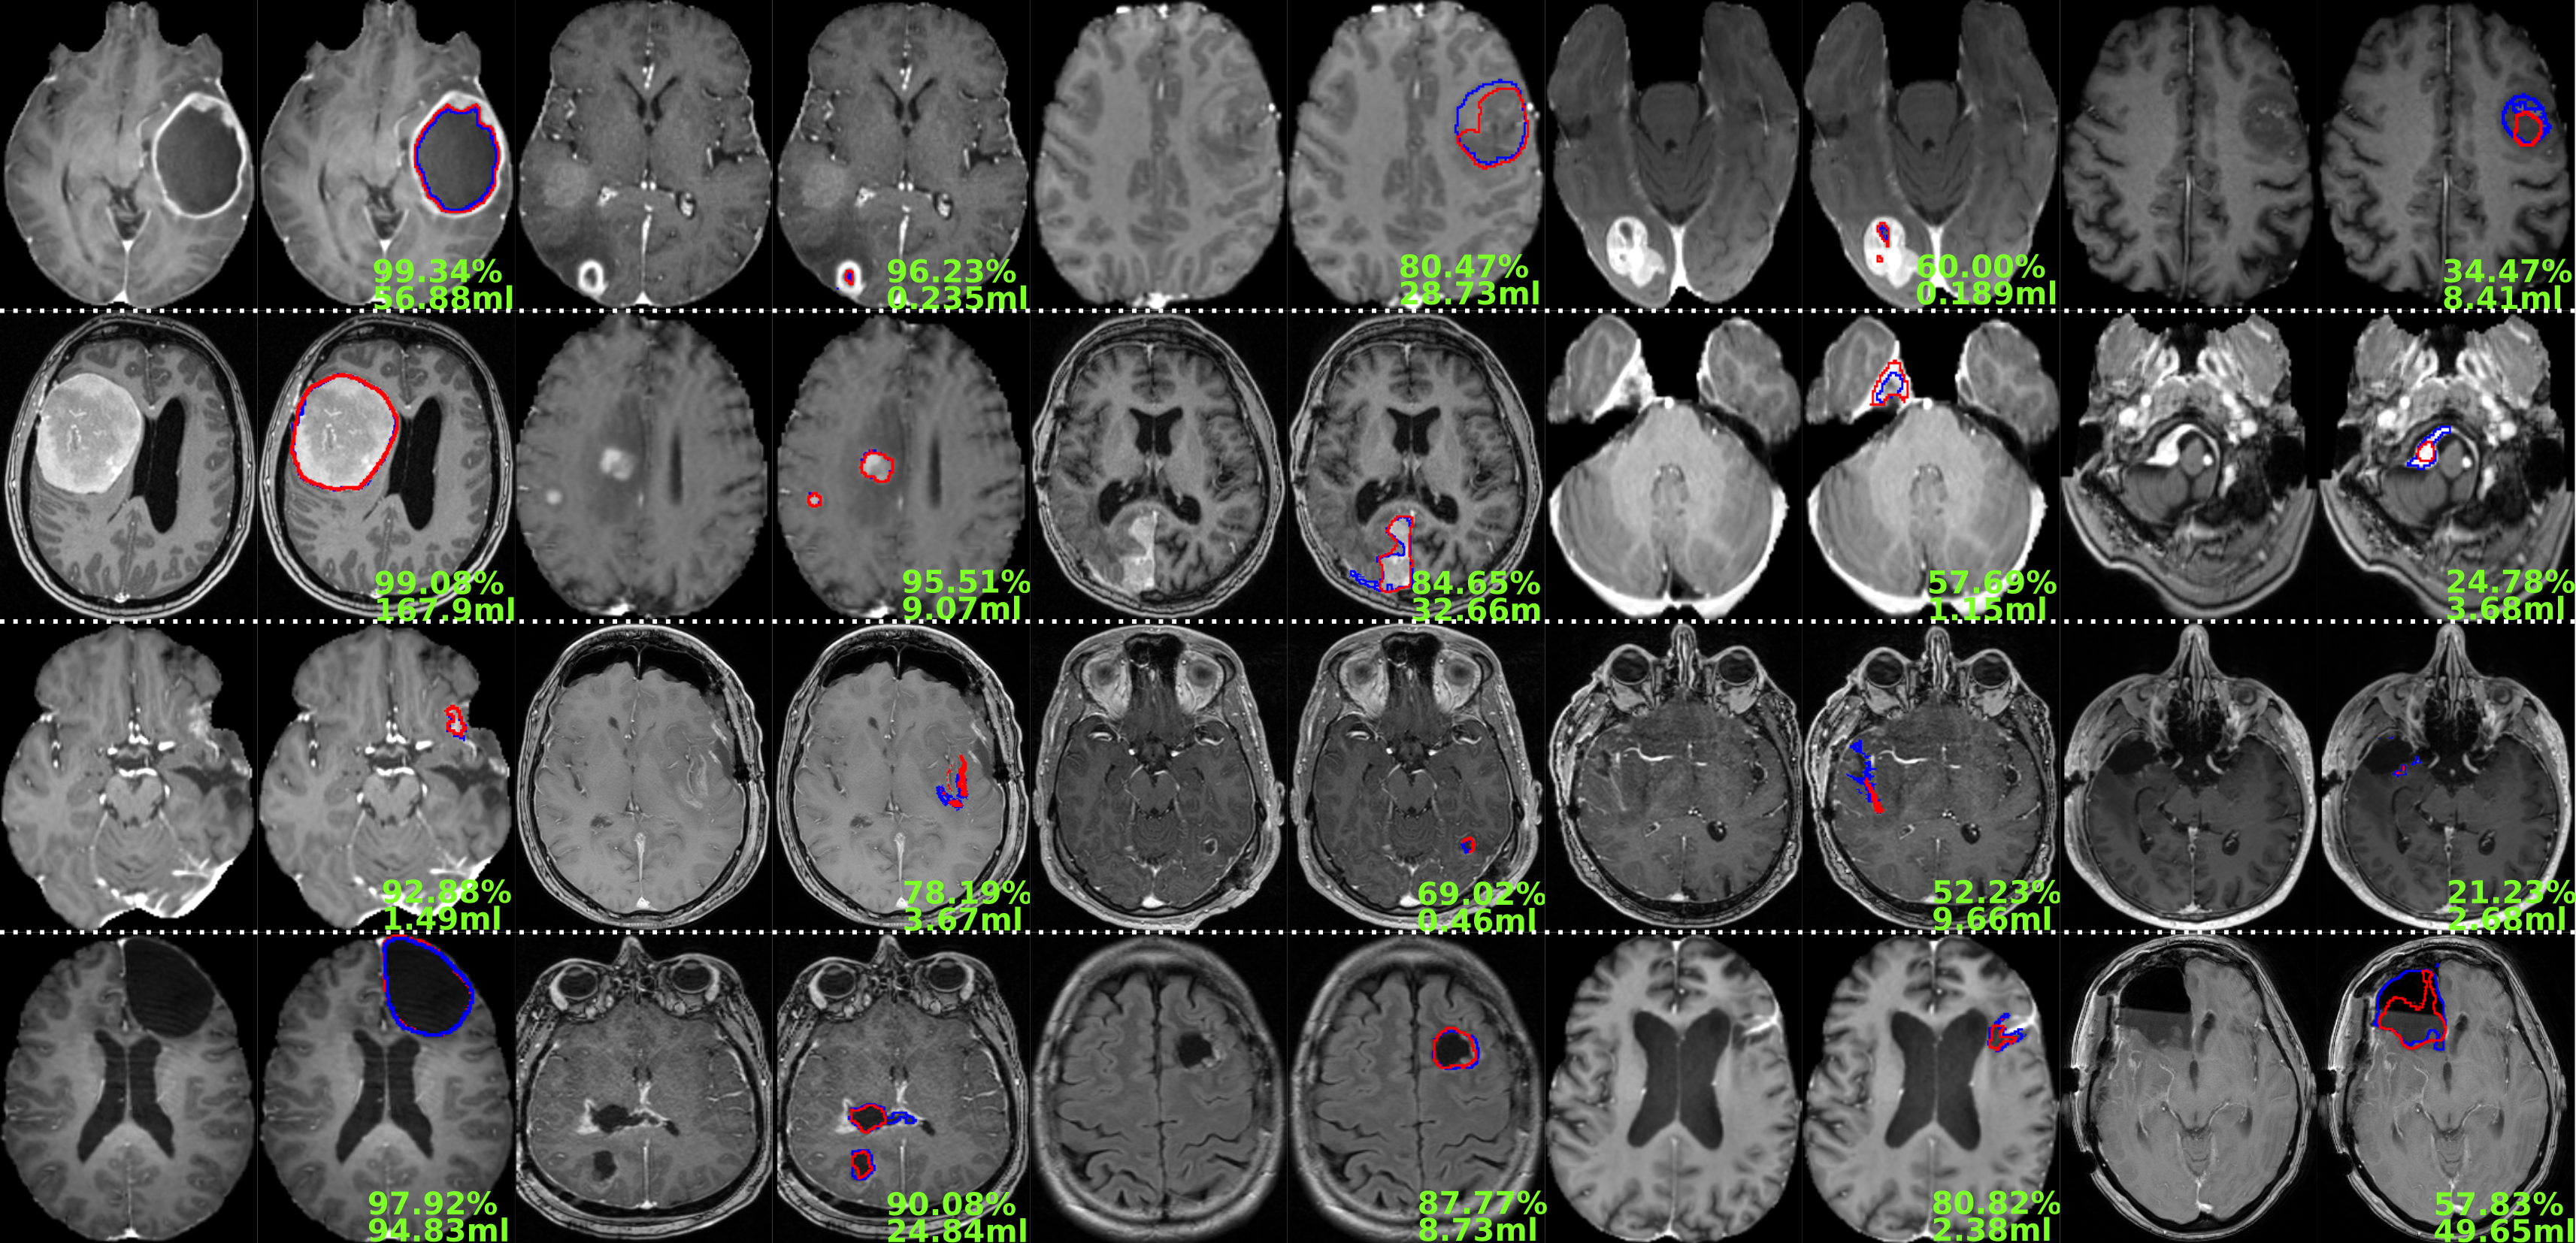

An overview of the models’ performance for each structure of interest is provided in Fig. 6, showing examples of best to worse results from left to right. For large tumors with a clear contrast-enhancing rim, the NETC model segmented almost perfectly with pixel-wise Dice scores above 95%. When the rim is not visible, potentially in presence of low-/non-contrast-enhancing tumors, the model tended to struggle. Regarding the contrast-enhancing tumor core segmentation model, clearly defined CNS tumors were almost perfectly segmented regardless of size (i.e., glioblastoma or metastasis). Identified cases of struggle often exhibit CNS tumors in unusual location (e.g., around the brain stem) not featured enough in the dataset. Next, the postoperative residual tumor model faced the challenge of segmenting small, fragmented, and not clearly confined structures. Oftentimes only part of the residual tumor was correctly segmented, omitting other smaller components around the cavity. The larger pieces of non-resected tumor, similar to the contrast-enhancing tumor core, were more easily segmented. Finally, the resection cavity segmentation model was more deficient when presented with inhomogeneous cavities displaying varying intensity levels (cf. right-most example in the last row of the figure).

Refer to caption

Figure 6: Illustration showing the ground truth (in blue) against the produced prediction (in red) for the NETC, tumor core, residual tumor, and resection cavity from top to bottom. The resulting Dice score and total volume to segment are given in green (image best viewed digitally and in color).